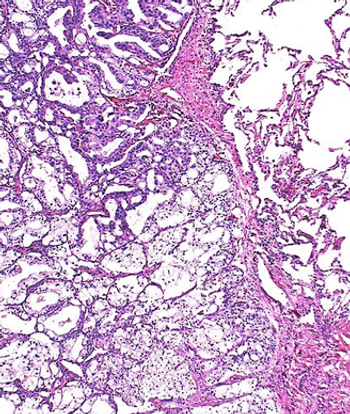

Prostate Cancer